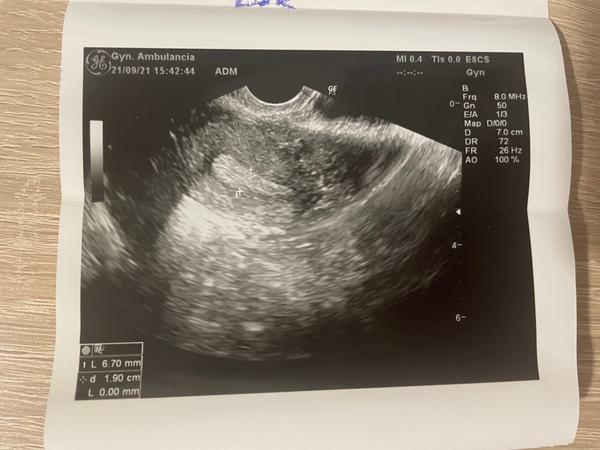

Aký problém je vidieť na fotkách zo sona?

mám 23 rokov a o dieťa sa snažíme dva mesiace. Doktorka ma poslala do CAR. Zatiaľ mi nebola nasadená žiadna liečba. Menštruačný cyklus mám 30 - 33 dňový.

USG bol spravený na 19. deň cyklu, krvné výsledky sú v poriadku.

Čo je vidieť na fotkách zo sona?

pri UZV vyšetrení vieme posúdiť ako vyzerá uterus, ovaria, či prítomné patológie v oblasti dutiny uteru, vajíčkovodov a ovárií.